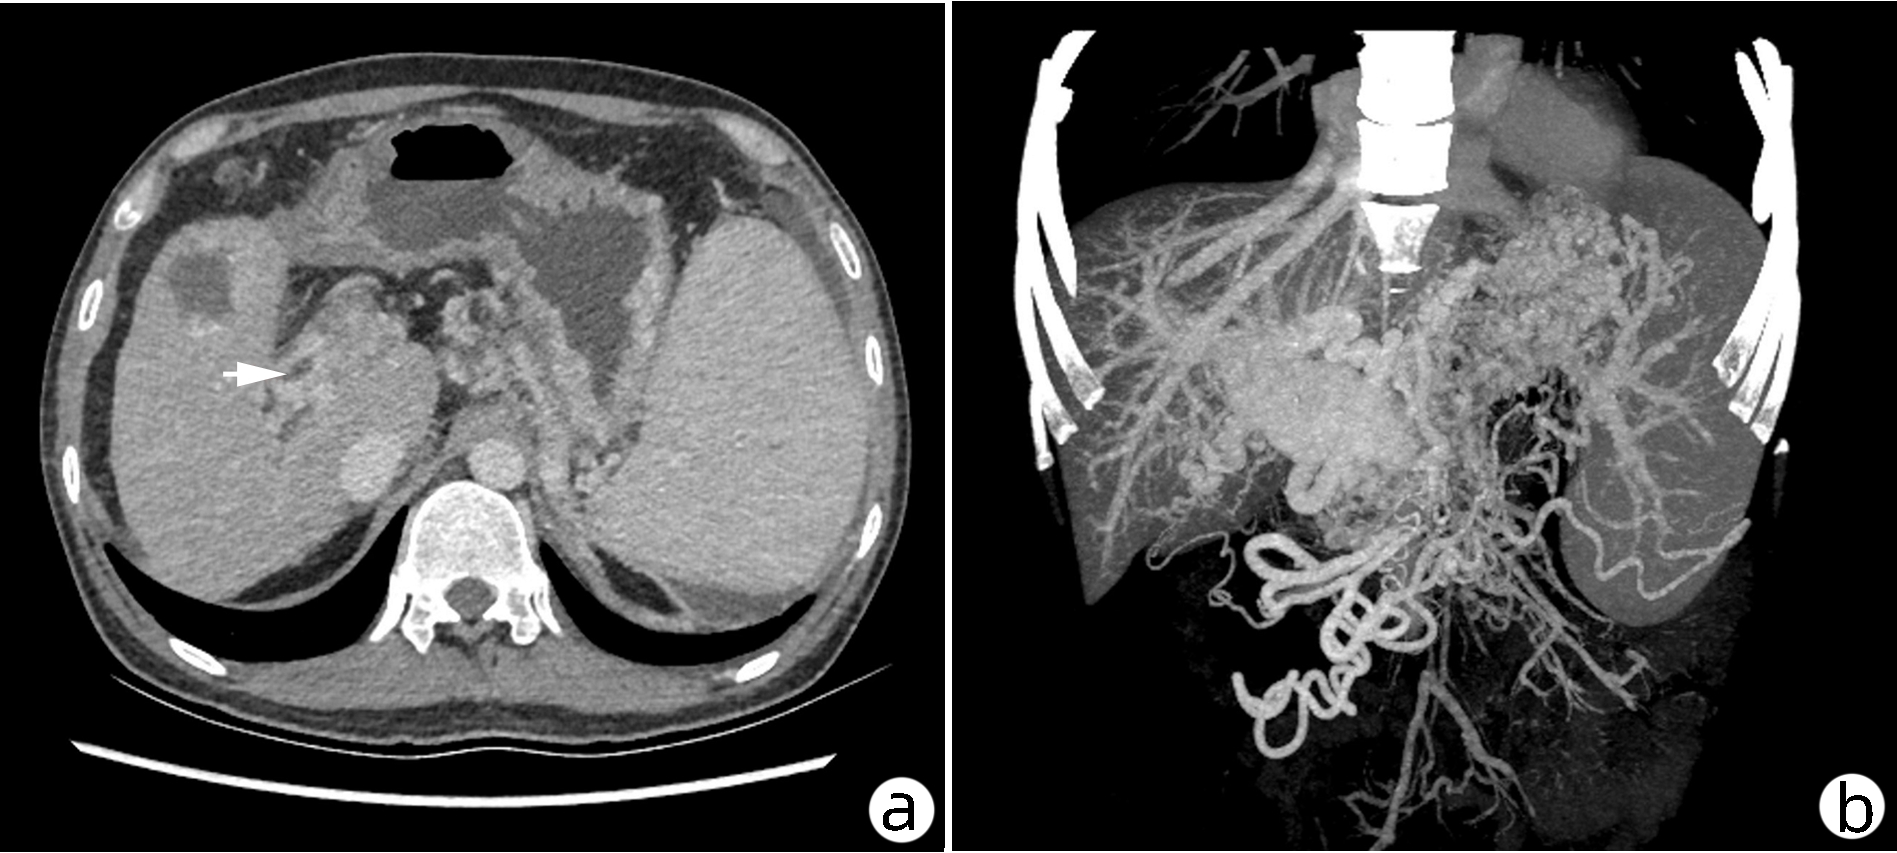

肝窦阻塞综合征成功诊治1例报告

耿雯倩, 朱浩, 杨鑫, 李婉玉, 许芳, 蔡艳俊, 高普均

2023, 39(2): 397-400. DOI: 10.3969/j.issn.1001-5256.2023.02.023

摘要(1455) HTML (476) PDF (2418KB)(134)

摘要: